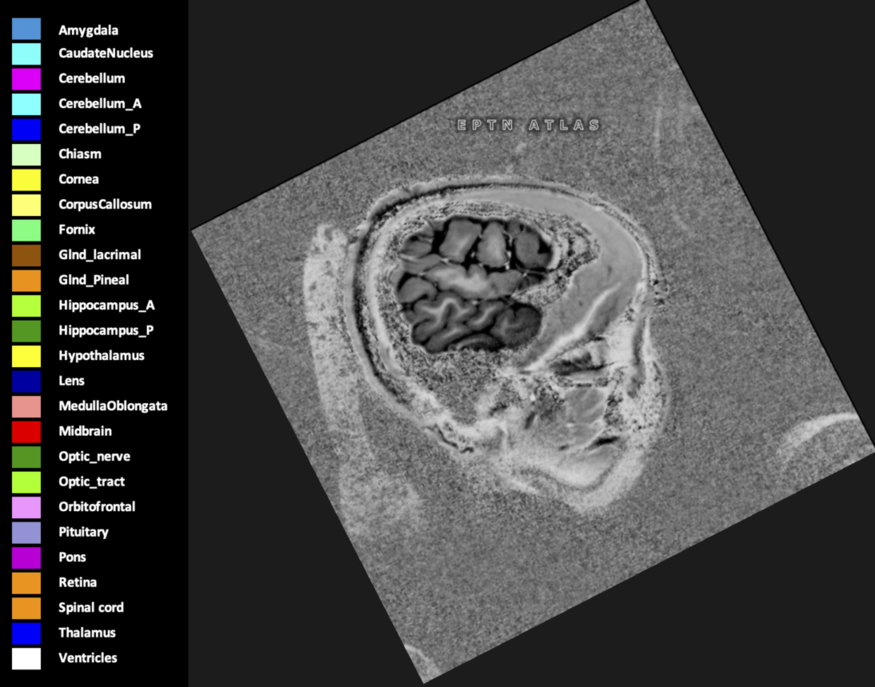

Three-dimensional delineation of the 25 consensus OARs for neuro-oncology are shown on CT (WW/WL 120/40, 3000/600), 3T MR images, (T1Gd, T2FLAIR 1mm) and 7T MR (MP2RAGE 0.7 mm). All are presented in transversal, sagittal and coronal view.